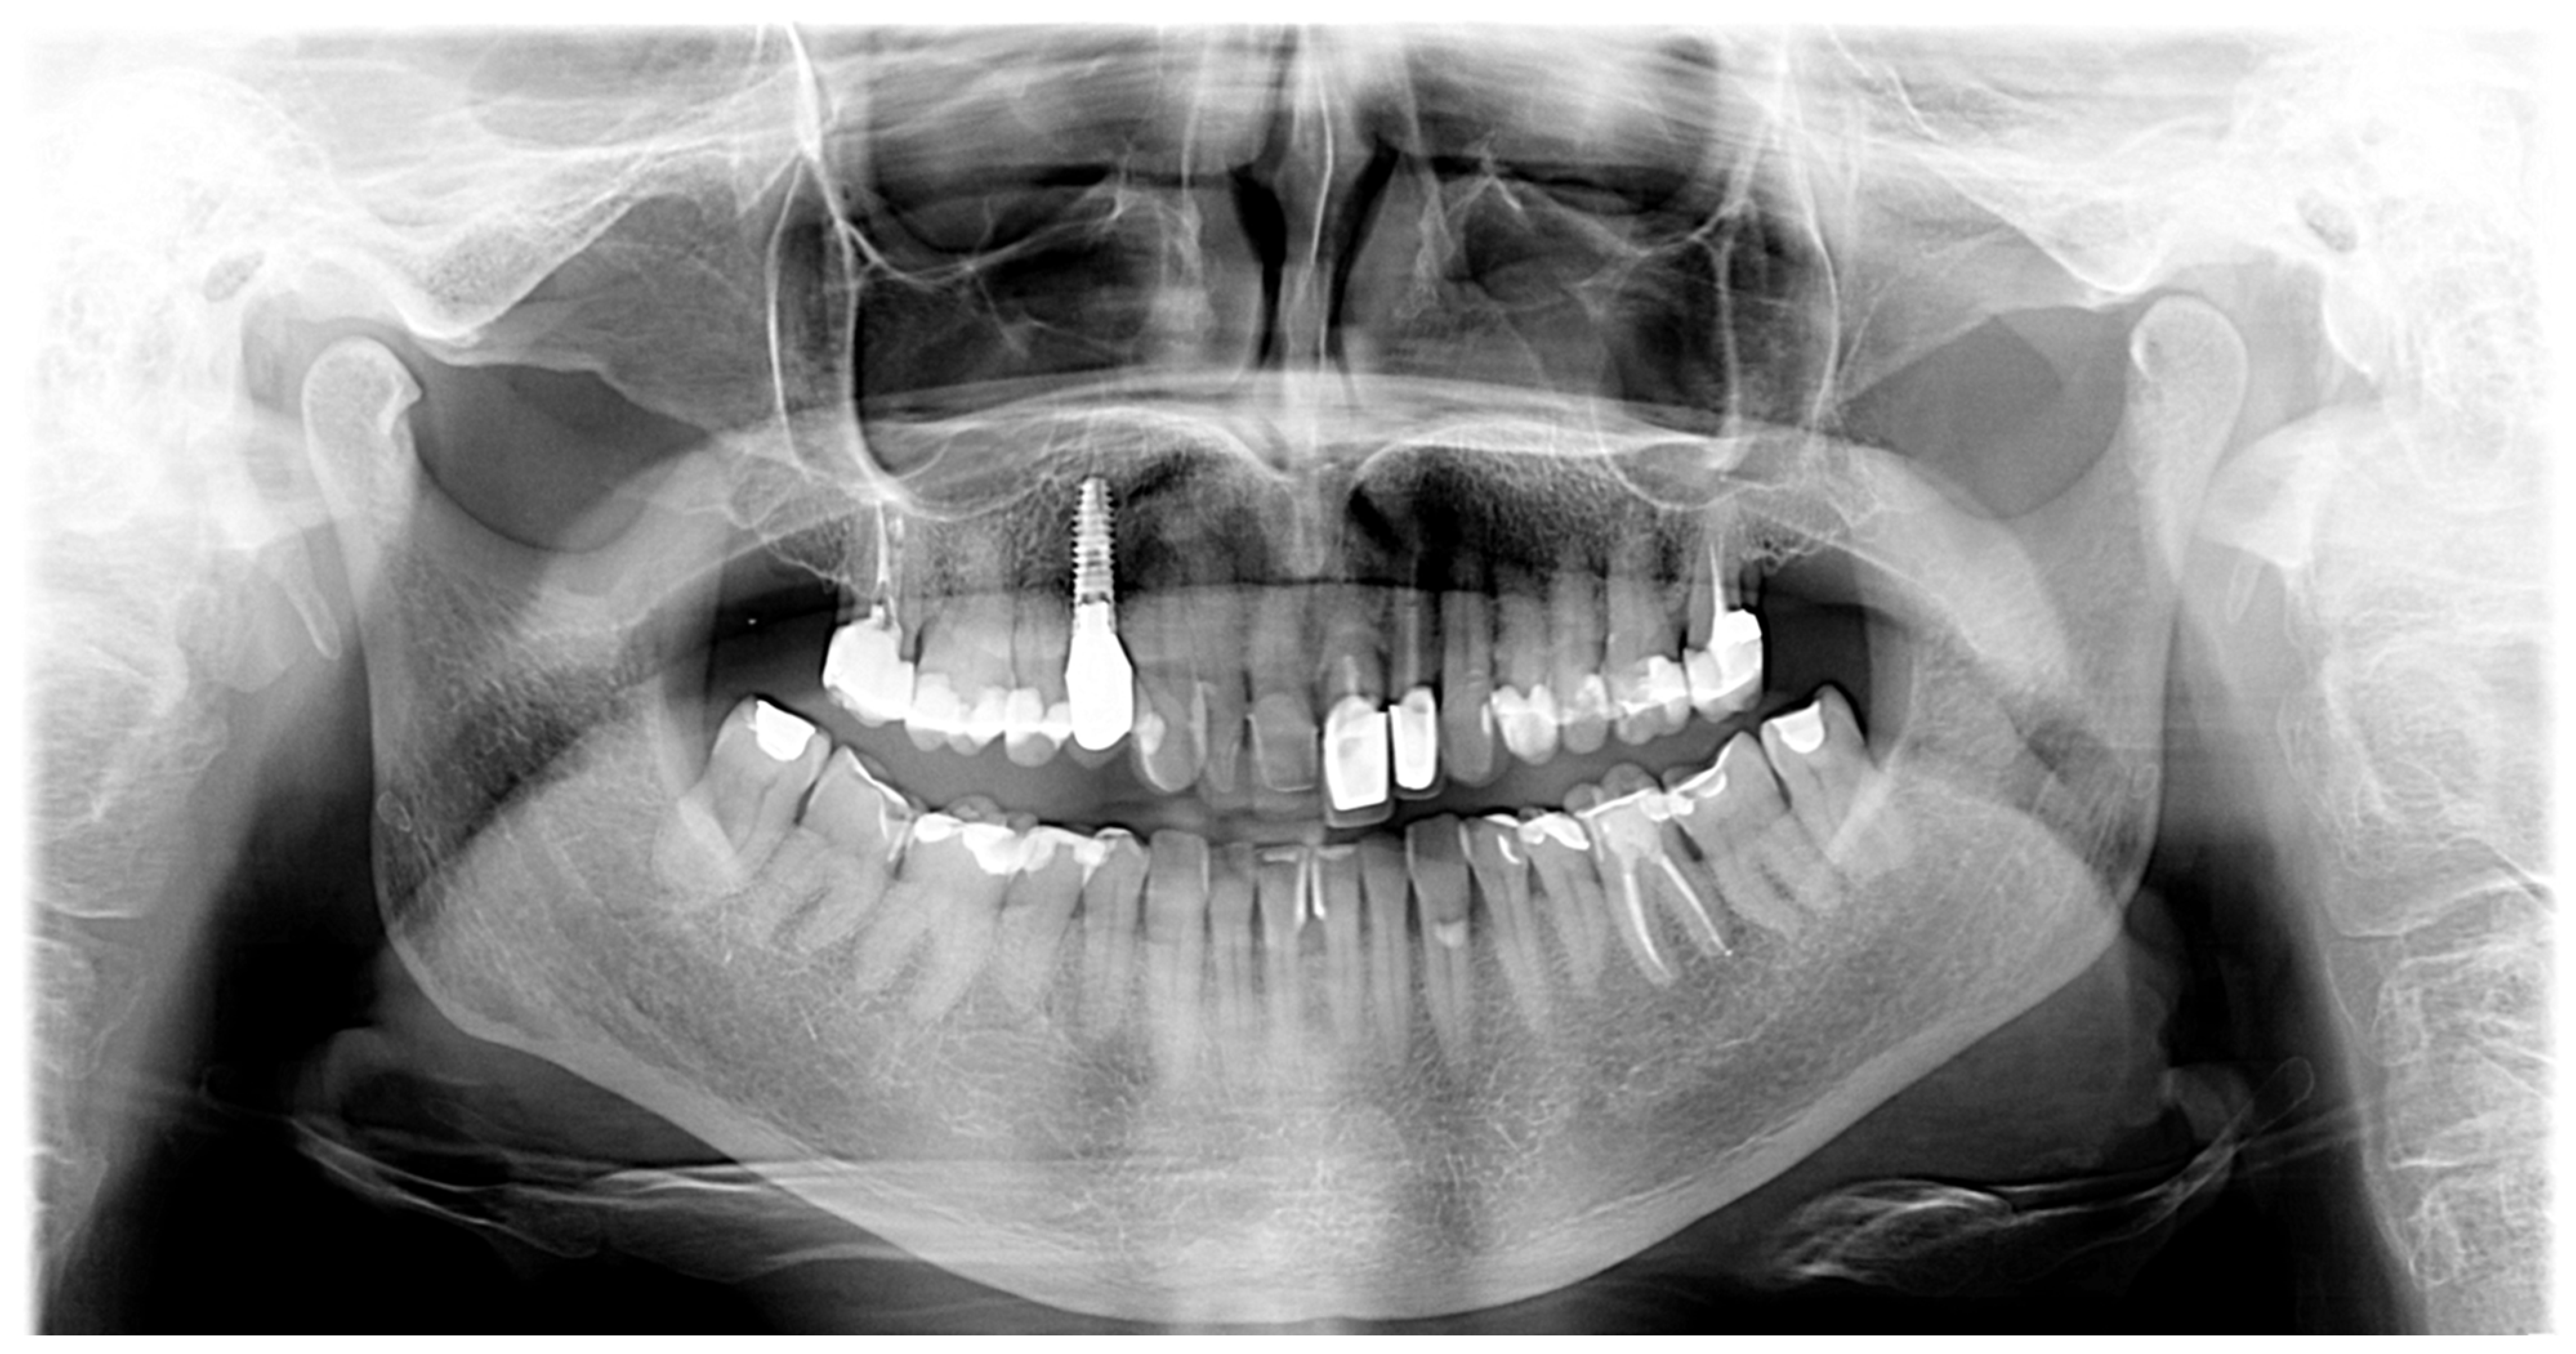

- Pretreatment occlusion scan using the iTeroTM 5.0 scanner, extracted into OrthoCAD 5.9.1.50 software (Align Technology, San Jose, CA, USA) (Figure 4), extra- and intraoral images taken with the Invisalign Practice App (Align Technology, San Jose, CA, USA) and pantomogram (Figure 5). Based on the iTeroTM 3D scan (Align Technology, San Jose, CA, USA) and occlusal examination, it was decided to use the Invisalign® system (Align Technology, San Jose, CA, USA) with the Express 1 arch subtype—the shortest possible treatment with seven aligners (and seven additional aligners) involving only the upper arch because the aim was to eliminate the occlusal injury of one tooth by its intrusion and a change of the anterior–posterior and mesiodistal inclination. The first treatment plan was performed using the ClinCheck 6.0 software (Align Technology, San Jose, CA, USA), which assumed movements of tooth 21—the main movement was a palatal inclination of the crown by 4.4 degrees, a distortion by 3.3 degrees and an intrusion by 0.4 mm (Figure 6). The analysis of this plan showed that it was impossible to eliminate the traumatic occlusion when changing the position of only one tooth in the arch (Figure 7)—the analysis showed numerous abnormal occlusal contacts.

Figure 5. Pantomogram—visible porcelain restorations and an implant in area 14.